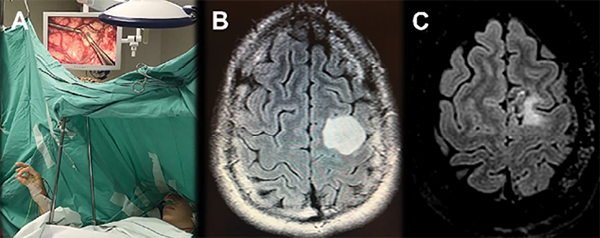

Figura 6. A. Ejercicio del área motora suplementaria y primaria (Tapping) en un tercer caso de una paciente femenina de 20 años, diestra, con diagnóstico de glioma de bajo grado en área premotora y motora primaria. La estimulación bloquea este ejercicio de coordinación. B. Cortes axiales de secuencia FLAIR de RMN prequirúrgica, en la cual se observa lesión glial de bajo grado hiperintensa en topografía de F1, F2 y giro precentral. C. Cortes axiales de secuencia FLAIR de RMN postquirúrgica, en la cual se observa pequeño remanente tumoral en F1 y giro precentral, debido a que la estimulación cortical en dichas áreas evocó una paresia del miembro superior derecho. La paciente evolucionó favorablemente, sin déficit motor, y retornó a una vida social y profesional normal, con una mejoría en su calidad de vida en comparación a las condiciones prequirúrgicas debido a convulsiones a repetición.